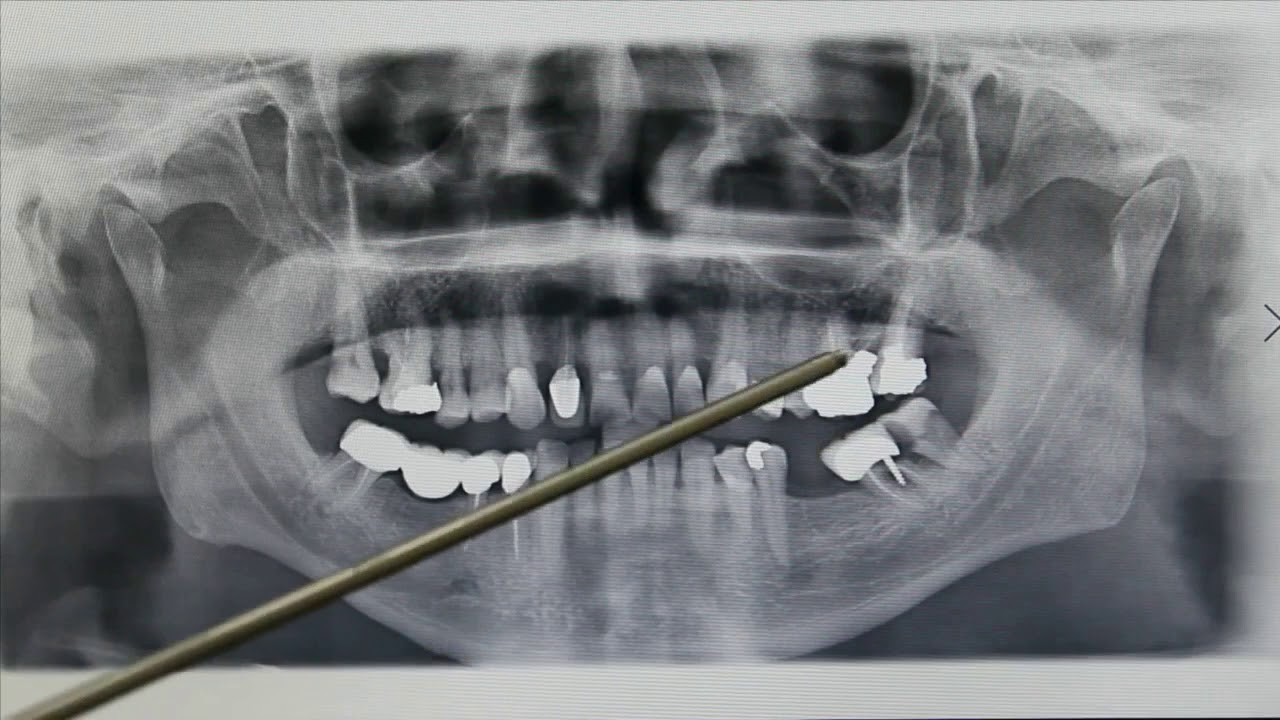

شكل خراج الأسنان في الأشعة

وفيما يخص شكل خراج الأسنان في الأشعة، فإنه يكون هناك بؤرة غامقة في الضرس تظهر في الأشعة السينية التي يجريها الطبيب قبل التدخل بوصف الدواء أو الجراحة، كما يحدد الطبيب من خلال الأشعة مدى انتشار الخراج في الأسنان المجاورة، وهناك مؤشرات تكشف أن المريض يعاني من خراج تكون كالآتي: